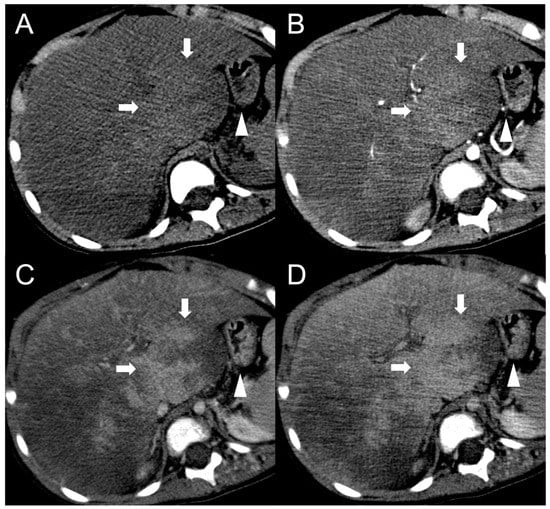

The presence of a central scar is another common finding in FNH-like RNs, particularly in those larger than 1 cm [10]. This scar typically appears as a hypointense, central stellate area on fat-suppressed T1-weighted imaging and a hyperintense area on T2-weighted imaging (Figure 2). Moreover, since regenerative nodules are made up of normal hepatocytes, they appear isointense or slightly hyperintense to the adjacent liver parenchyma on diffusion-weighted imaging, and there is no significant reduction in the diffusion values observed on the ADC map. These characteristics help to differentiate between regenerative and HCC nodules with reasonable confidence in patients with BCS.

Figure 2.

FNH-like RN with central scar (arrow) in a 34-year-old male patient with Budd–Chiari syndrome. In MRI, the scar is typically hyperintense on fat-saturated T2-weighted images (A) and hypointense in T1-weighted images (B). In the arterial phase after contrast agent administration, the scar can be identified as a central stellate area that appears hypodense in CT (C) and hypointense in MRI (D). In the CT delayed phase, the nodule shows increased density, but a central hypodense component representing the scar remains visible (E). In gradient-echo T1-weighted images acquired in the hepatobiliary phase (F), the scar is clearly depicted as a central low-signal area.

Besides changes in size, as mentioned above, the MRI features of FNH-like RNs can alter during the follow-up period (Figure 4). For example, the T1 and T2 signal intensity may change, more frequently with a shift from hyperintense to isointense on T1-weighted images and from hypointense to isointense on T2-weighted images. The enhancement pattern may vary as well, with washout acquired in 8% of cases and lost in nearly 20% of cases.

Figure 4.

MRI examinations of a 31-year-old male patient with Budd-Chiari syndrome performed in 2016 (A), 2017 (B), 2018 (C), and 2020 (D). Gradient-echo T1-weighted sequences (flip angle = 30°) acquired in the hepatobiliary phase revealed a 25 mm FNH-like RN (arrows) with central scar and peripheral hyperintensity in 2016 (A). The lesion size grew to 41 mm after 1 year (B) and further to 44 mm after 2 years (C), but it reduced to 35 mm in 2020 (D). Additionally, new FNH-like RNs appeared over time (arrowheads in C,D).